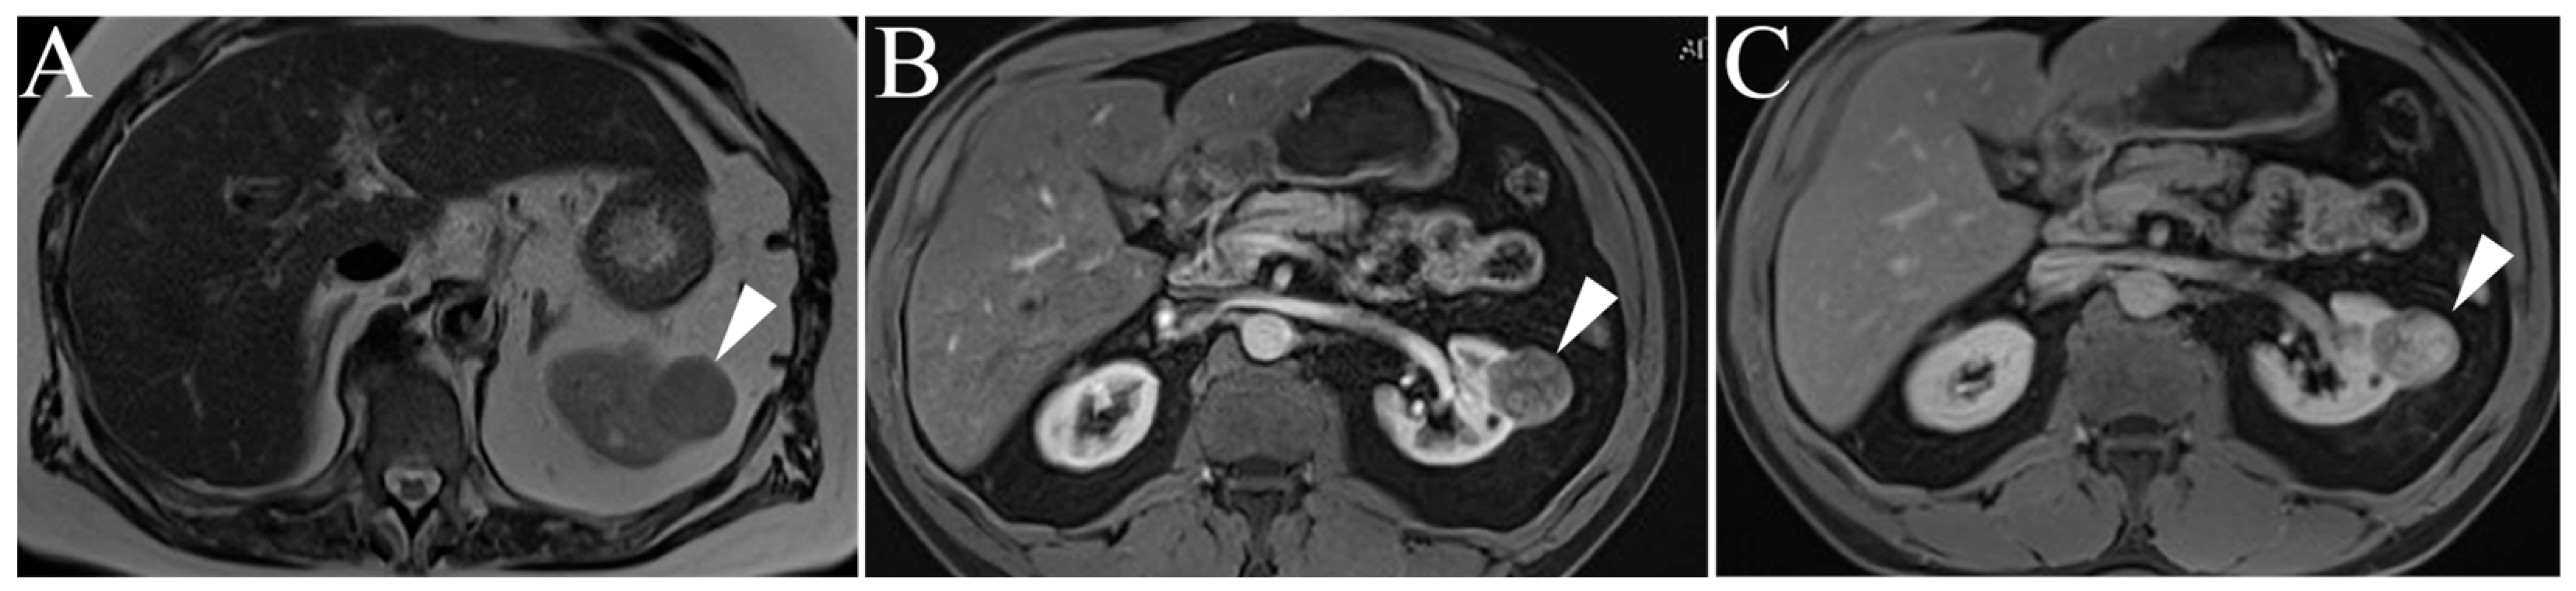

6.1. Lymphoma

6.2. Metastases

6.3. Transitional Cell Carcinoma

| Renal Lymphoma | Low to intermediate T1 and T2 signal intensity Mild, delayed, homogenous enhancement Multiple 1–3 cm solitary masses |

| Metastasis | Varied presentation, usually identical to primary tumor Multiple, atypical renal masses History of advanced, non-renal malignancy |

| Transitional Cell Carcinoma | Intermediate T1 and T2 signal intensity Delayed, heterogenous enhancement Filling defects and soft masses when urine is present as contrast medium |